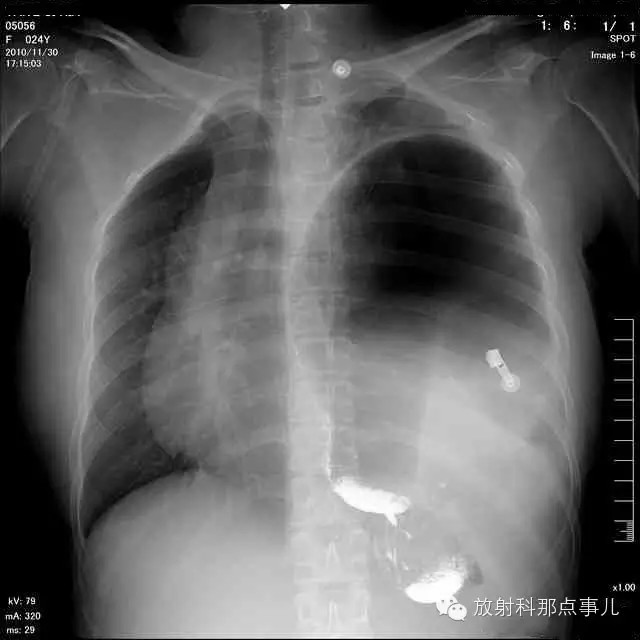

门诊腹部透视发现左侧胸腔巨大气液平面,为排除膈疝口服钡剂,但造影剂未见进入胃内。嘱住院,外科给予胃肠减压、补液等处理常规处理(未引流出明显气、液体)。5个半小时后再次检查,见少量造影剂进入消化道;为进一步了解情况,予泛影葡胺分别经胃管推注及口服,但均未进入胃内。当天进行外科急诊手术。

大部分胃、脾及横结肠均经过胸肋三角疝入左侧胸腔内,并见疝环形成。

考虑该患者因生产过程中腹压急剧升高,导致腹内脏器经膈肌缺损或薄弱部位进入胸腔内。